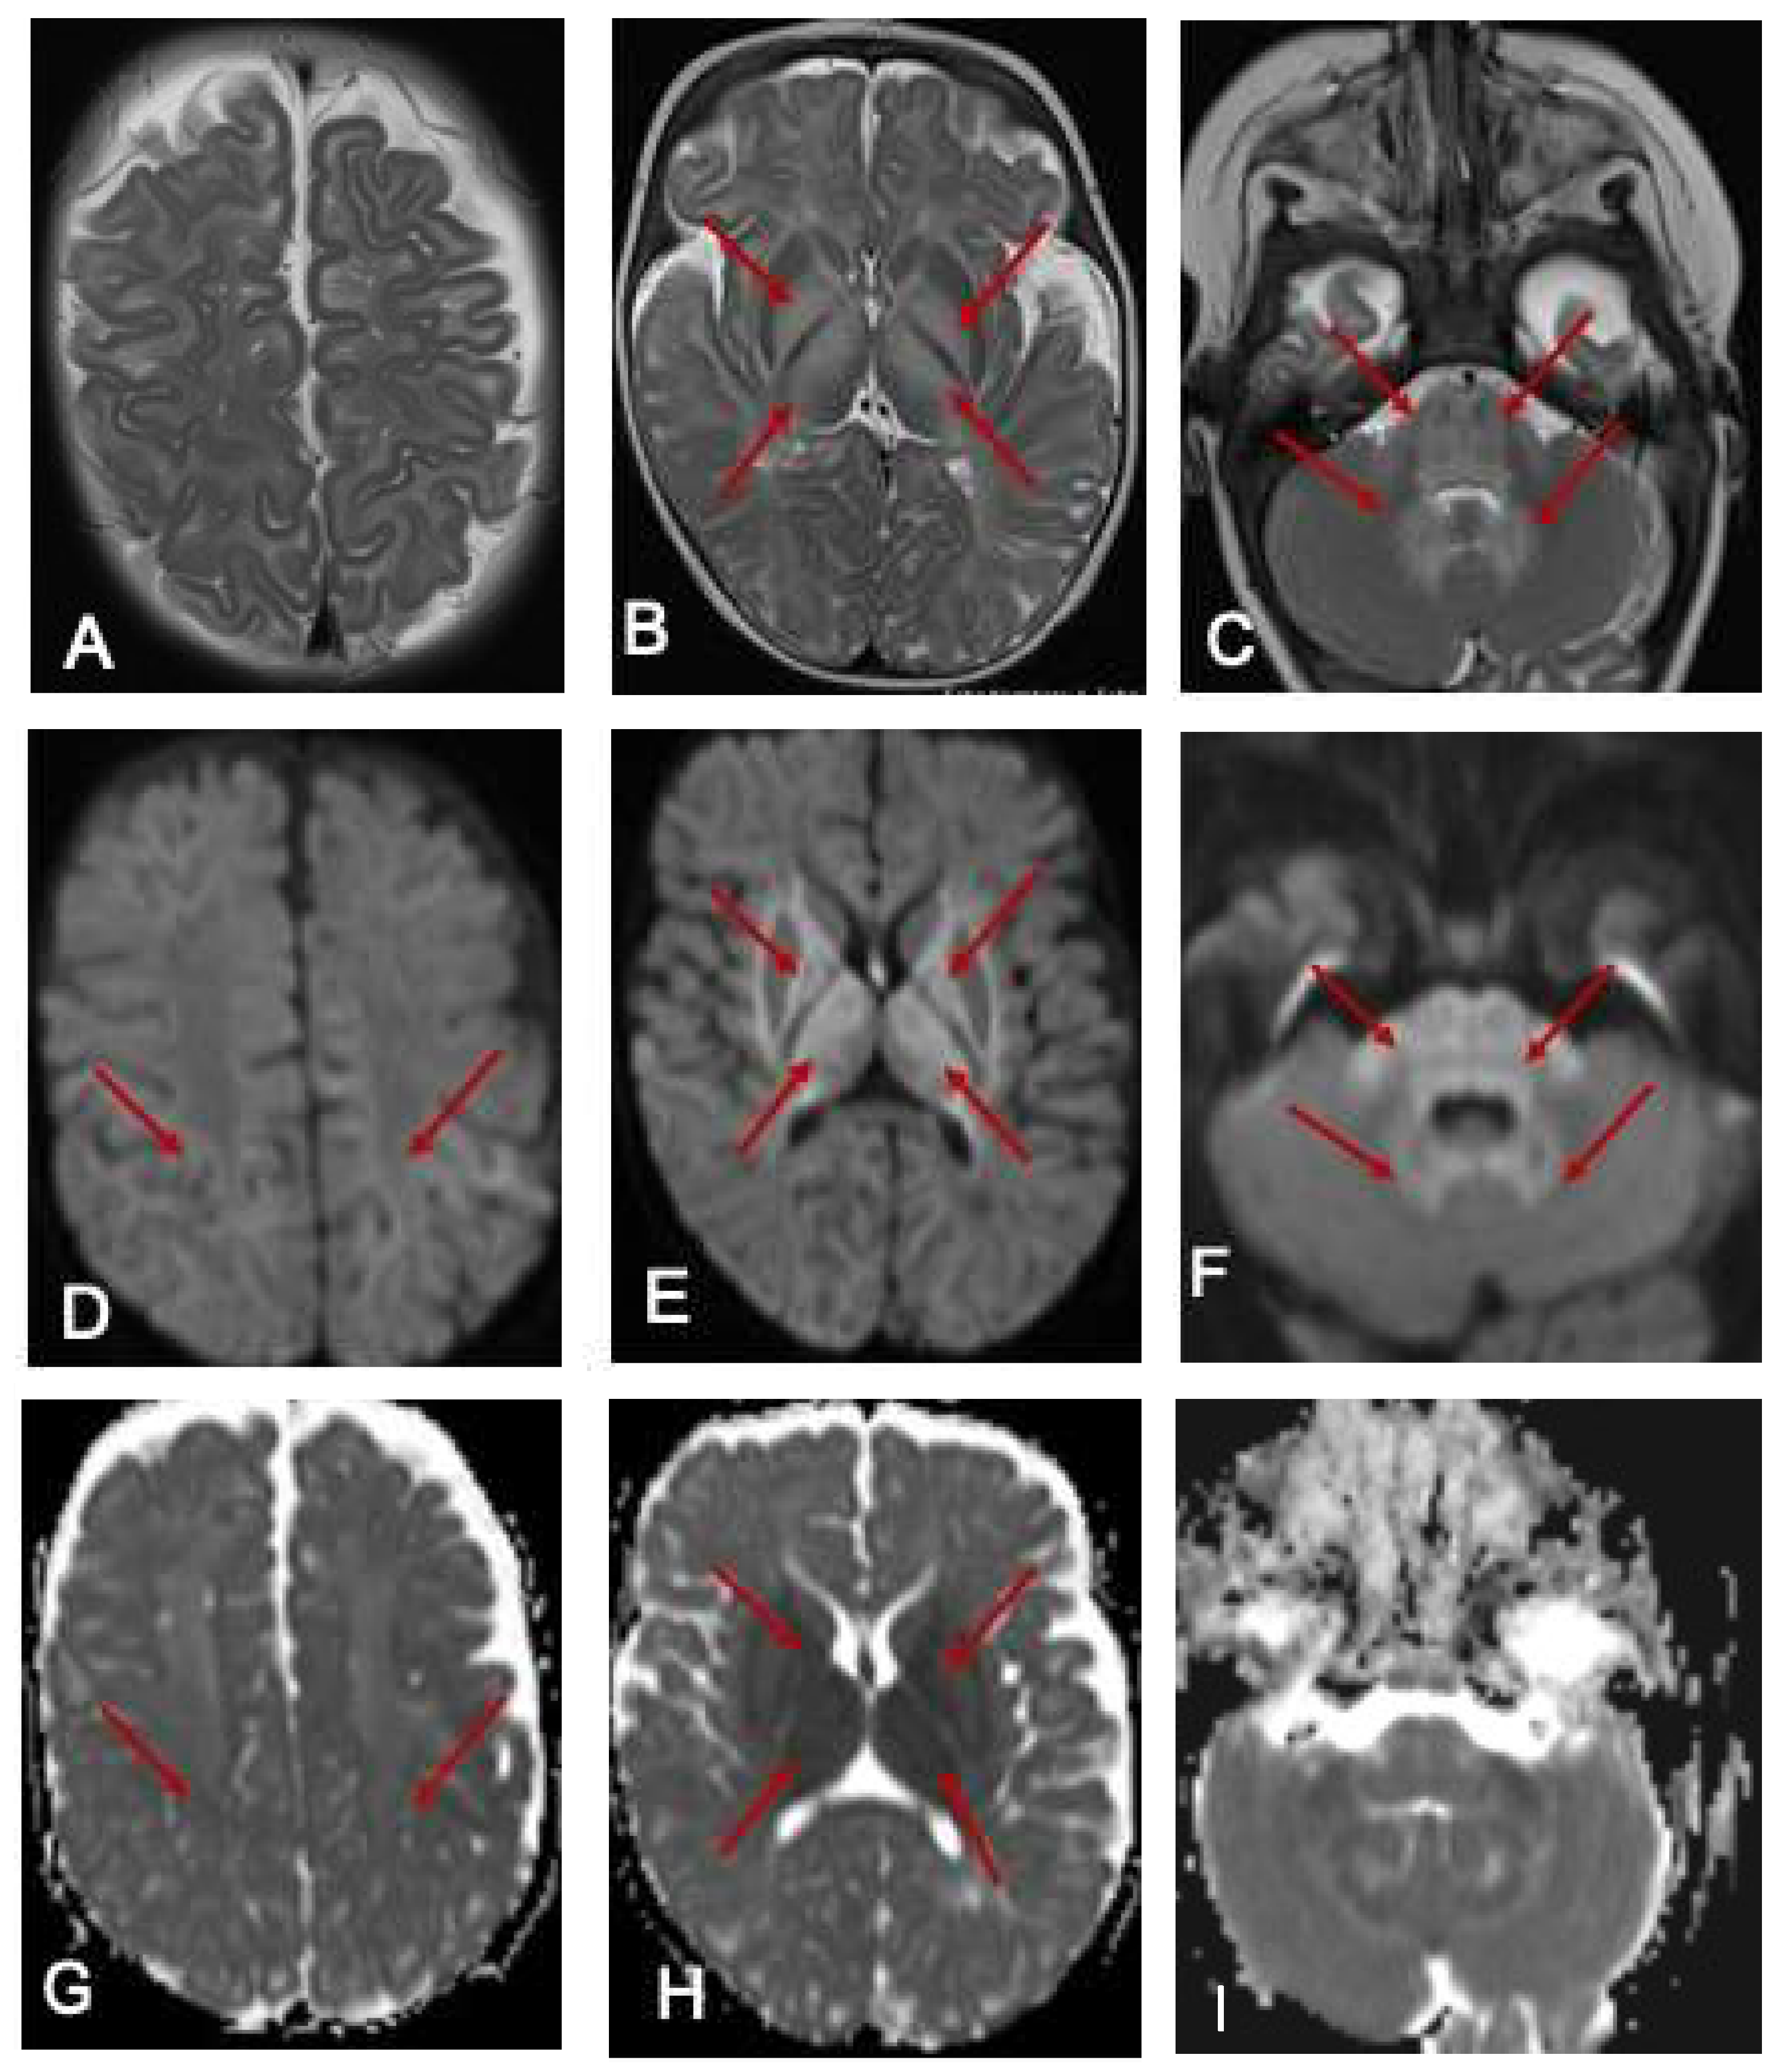

Ammonia was 113 μmol/L (10–50 μmol/L). She commenced intravenous dextrose 10% containing fluids and lipids in the acute setting, oral thiamine supplementation, a protein-restricted diet and MSUD-specific, BCAA-free formula (MSUD Anamix Infant, Nutricia Australia). MRI of the brain demonstrated bilateral symmetrical T2 hyperintense signal changes involving the white matter globus pallidus thalamus brainstem and dentate nuclei with restricted diffusion (Figure 1). EEG was mildly abnormal, with intermittent slowing (2–3 Hz amplitude slowing) noted bilaterally and unilaterally in the posterior and frontal regions with occasional generalised bursts and occasional right centrotemporal sharp transients. She responded well to the dietary intervention and was discharged home with residual neurological sequelae including hypotonia and continued involuntary limb movements, which were assessed to be myoclonic jerks.

Figure 1.

MRI of the brain at 7 months. The red arrows show the hyperintense signal changes. T2-weighted axial images of an MRI scan of the brain at 7 months of age (A–C) show hyperintense signal changes in the white matter (A), globus pallidus (B), and thalamus (B); pons, cerebellar peduncle, and dentate nucleus (C arrows). The corresponding areas show restricted diffusion in DWI Images (D–F) and ADC maps (G–I).